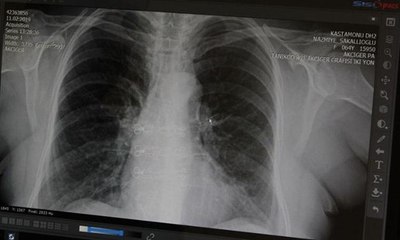

Karabük'te öksürük şikayetiyle hastaneye başvuran bir kadının tomografilerinin çekilmesi sonucu akciğerinde yabancı bir cisme rastlandı. Hemen ameliyata alınan kadının akciğerinden kabak çekirdeği çıkarıldı. Doç. Dr. Murat Acat, "Bana öksürük şikayetiyle geldi. Bronkoskopi yaptım ve yabancı bir cisim gördüm. Sonra biyopsi pensi ile çıkardım. Çıkarınca kabak çekirdeği olduğunu gördük ve çok şaşırdık" dedi. brpBirkaç aydır öksürük şikayeti olan Hatice U. (56), Karabük Üniversitesi Eğitim ve Araştırma Hastanesine başvurdu. Göğüs Hastalıkları Uzmanı Doç. Dr. Murat Acat ve ekibi, çekilen tomografilerde akciğerde yabancı bir cisim bulunduğunu tespit etti.pAKCİĞERİNDEN KABAK ÇEKİRDEĞİ ÇIKTIpHemen ameliyata alınan kadının akciğerinden kabak çekirdeği çıkarıldı. Acat, gazetecilere yaptığı açıklamada, hastanın sağlık durumunun iyi olduğunu belirterek, "Hasta aylar önce kabak çekirdeği yemiş. Bana öksürük şikayetiyle geldi. Akciğer tomografisinde lezyon görünüyordu.